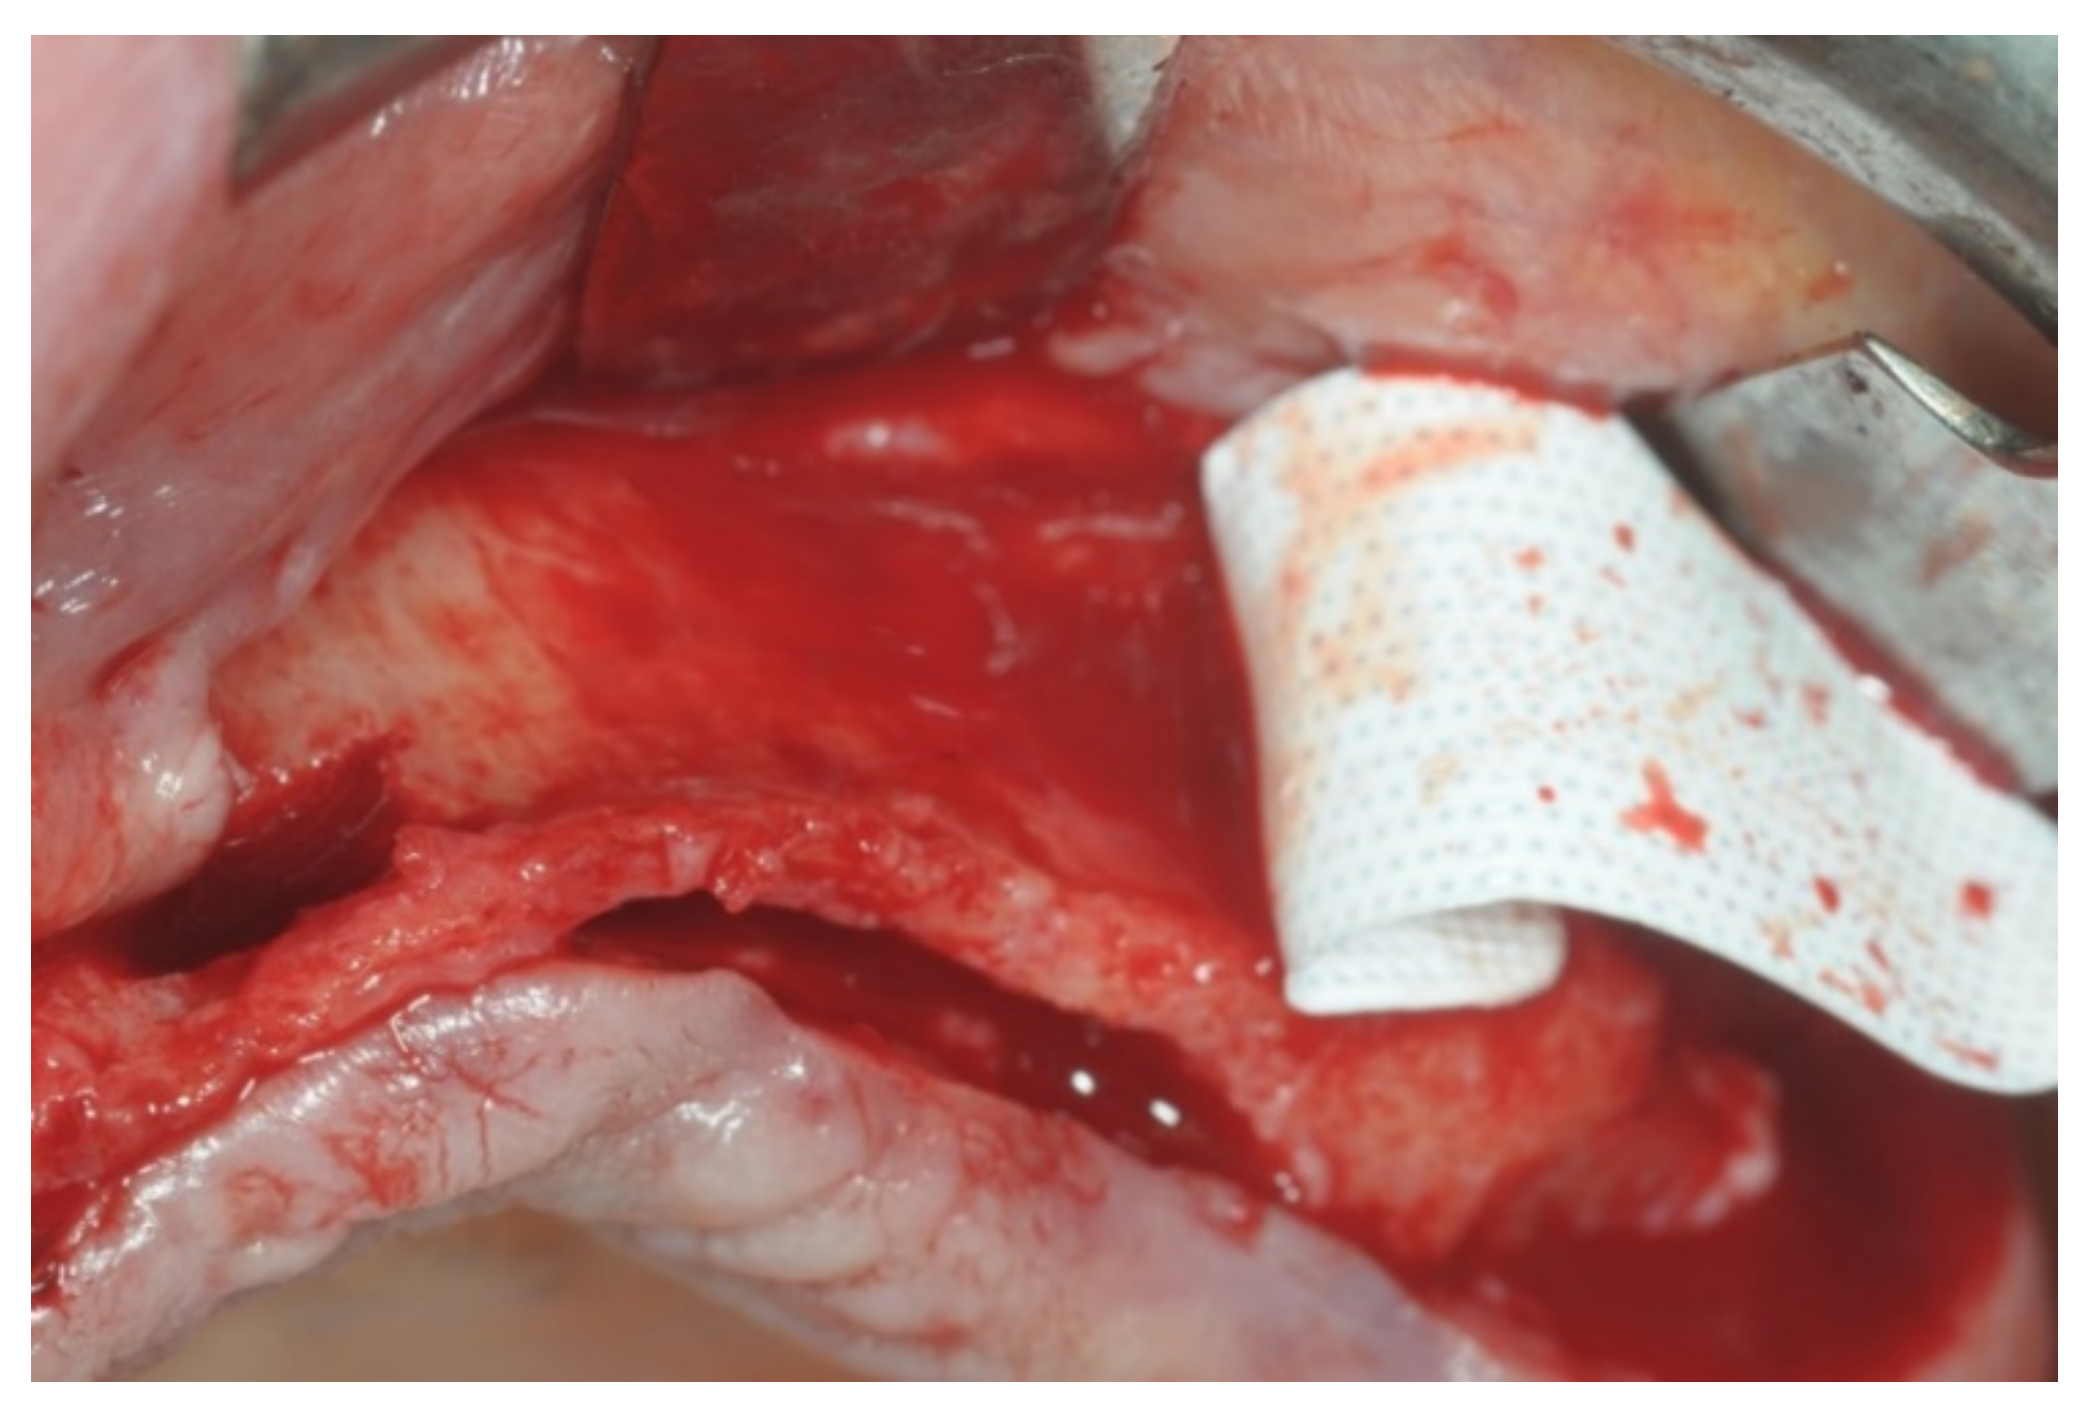

At this point, a non-resorbable high-density PTFE barrier (Cytoplast TXT-200, Osteogenics Biomedical, Lubbock, TX, USA) was designed on the basis of the bone defect shape and was distally blocked on the bone by two titanium pins (Kalos, Nike, Orbetello, Italy). A mixture of 50% autogenous bone harvested from the mandibular ramus with the use of a scraper and 50% inorganic bovine bone (Bio-Oss, Geistlich, Wolhusen, Switzerland) was placed in the recipient site and the membrane was pulled and blocked on the bone with two mesial pins. With this particular, and innovative, non-resorbable membrane management, the graft was compressed and fixed on the recipient bed (Figure 9, Figure 10 and Figure 11). The occlusal portion of the graft was then covered with a layer of a collagen resorbable barrier (Bio-Gide, Geistlich) (Figure 12) and peri-osteal incisions were performed to make the flap passive.

Patients rinsed with a chlorhexidine mouthwash (0.2%) for 1 min immediately prior to the intervention. Local anesthesia were administered using mepivacaine with adrenaline at ratios of 1:100,000 or 1:50,000. Crestal incisions were made with releasing incisions far away from the future membrane positioning and full thickness flaps were elevated. After the meticulous removal of all residual soft tissues in the regenerating site, copious bleeding was induced using a bone scraper (Safescraper Curve TWIST, META, Reggio Emilia, Italy) (Figure 1). A prosthetically guided implant placement was performed following the instructions of manufacturer (Thommen Medical, Grenchen, Switzerland). Only 1 patient had implants placed 9 months after bone augmentation because the initial bone thickness did not permit the primary stabilization of the implant fixtures (Figure 2, Figure 3, Figure 4, Figure 5, Figure 6, Figure 7 and Figure 8).

Figure 10. Frontal view of the area to be augmented with the “sling technique”.

Figure 12. Placement of the collagen resorbable membrane covering the occlusal portion of the graft below the future suturing line.